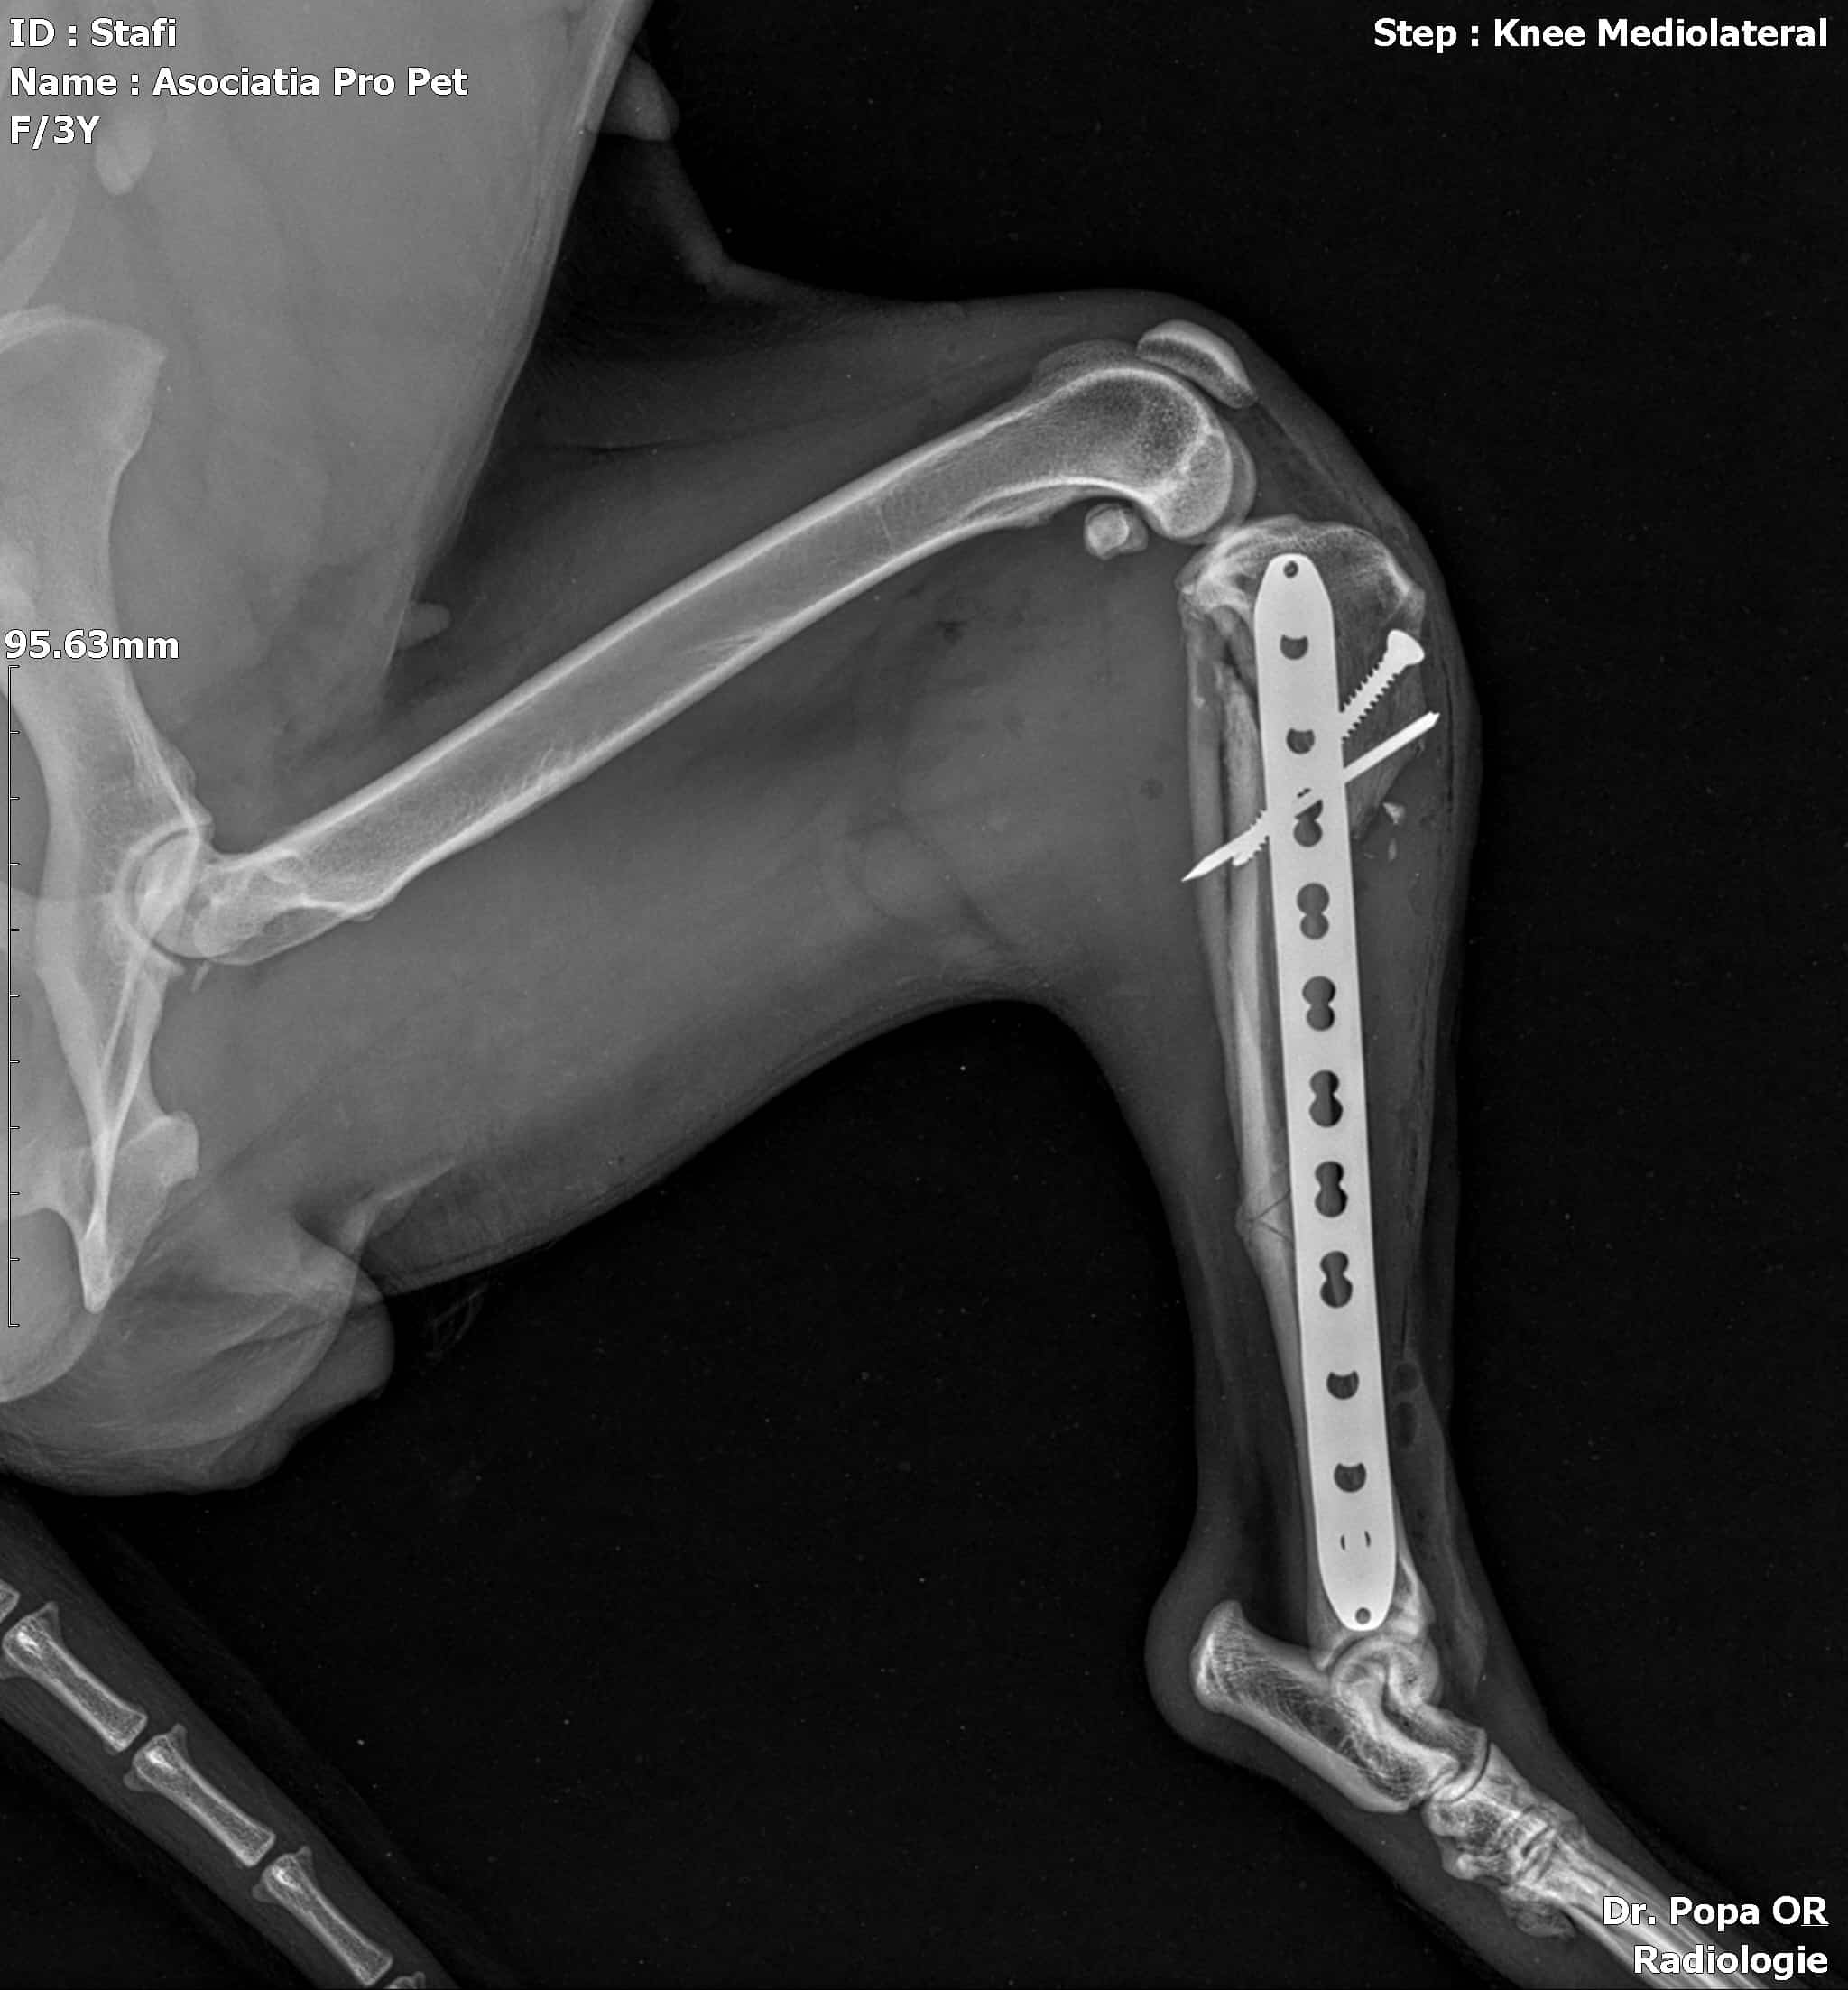

Jubina im Vet-House ist operiert, total menschenbezogen und verschmust und sehr sehr dünn. Wenn sie da raus muss, hat sie sicher wenig Chancen..

Röntgenbilder nach OP zugefügt.

JUBINA wurde angefahren und hat einen gebrochenen Hinterlauf, der zeitnah operiert wird (10/2022).

Beinbruch nach Autounfall, wurde operiert, aktuell viel zu dünn (10/22)